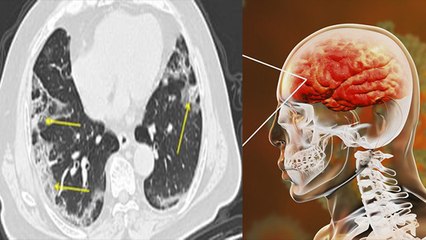

एसएमएस अस्पताल के ENT विभाग में रोजाना 8-10 प्रतिशत ऐसे मरीज पहुंच रहे हैं, जिनकी श्रवण क्षमता को ध्वनि प्रदूषण के कारण नुकसान पहुंचा है.